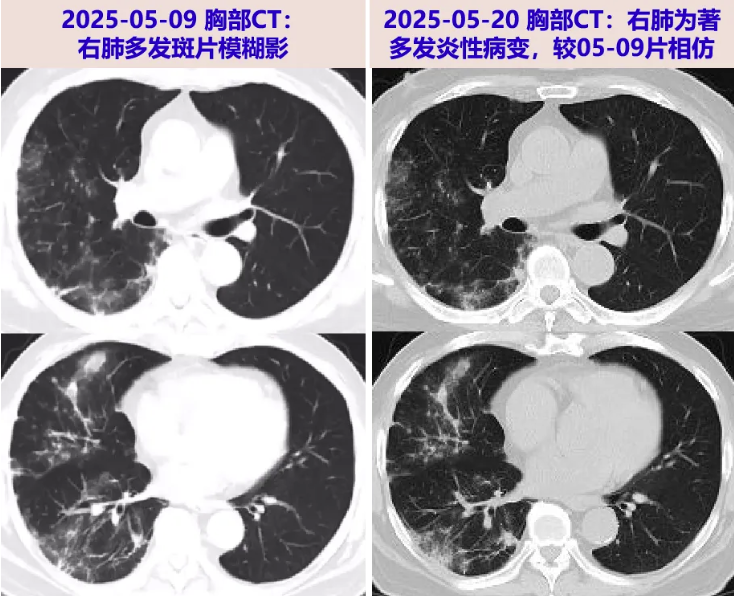

2025-05-09 就诊于当地医院,查WBC 9.93×10^9/L,N% 77.2%,Hb 73g/L;CRP 6.4mg/L,sCr 232μmol/L;血隐球菌荚膜抗原阳性。胸部CT:右肺多发斑片模糊影,考虑炎症,两肺散在磨玻璃结节;予莫西沙星0.4g qd经验性抗感染。

胸部CT:右肺为著见多发斑片、小结节改变,部分纤维条索样病灶。

2025-05-26 肺组织病理免疫组化及特殊染色:考虑真菌感染,隐球菌可能;随访血常规:WBC 9.68×10^9/L,N 80.5%,L 1.2×10^9/L,Hb 80g/L;炎症标志物: ESR 28mm/h,hsCRP 19.6mg/L,PCT 0.09ng/mL;Cr 206μmol/L ;胸部CT:右肺为著多发炎性病变,较05-20大致相仿。